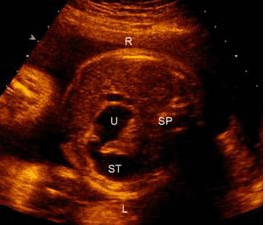

孕妇,36岁,孕1产0孕23周2d。孕16周血清学唐氏综合征筛查风险值为1/60。超声测量羊水指数为26cm,上腹部横切面超声所见如下图。

(R-右侧,L-左侧,U-十二指肠,ST-胃泡,SP-脊柱)

为了明确该胎儿是否患有染色体异常,应检查()。

A.进一步详细超声检查,并对胎儿进行基因诊断

根据病史及声像图表现,最合适的诊断为()。

该畸形最可能合并的染色体异常为()。

进行更详细的超声检查,不属于重点检查的部位是()。